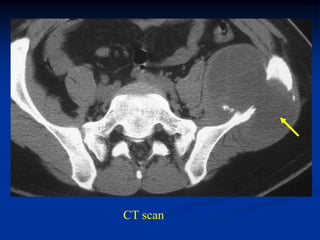

Case #1161.1              Endometrial CA

57 year female with leg and heal pain for one year

Post op cemented IM nail